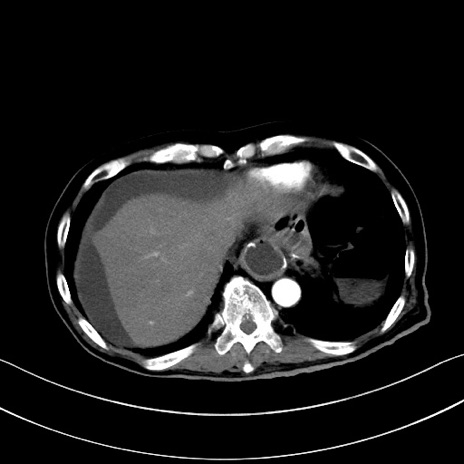

冠状断像